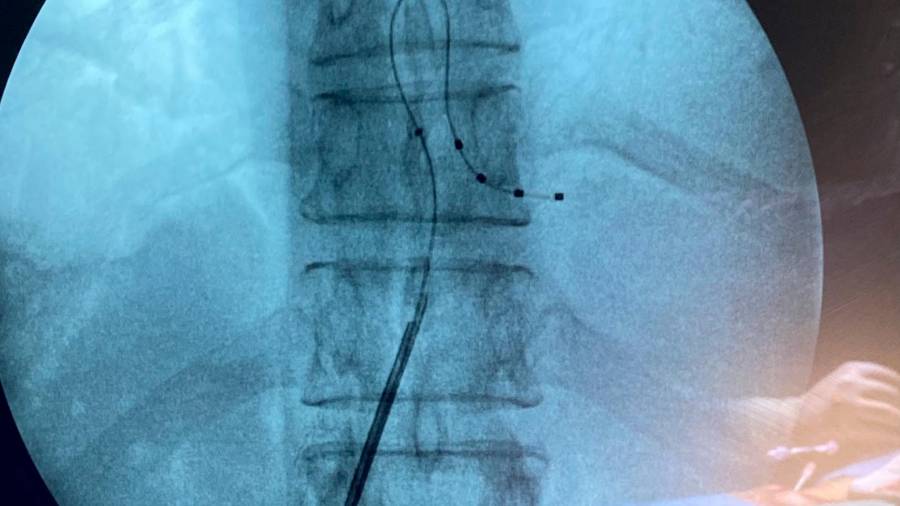

<i>Electrodo implantado en el hosital ubetense. / Juan de Andalucía. </i>

Electrodo implantado en el hosital ubetense. / Juan de Andalucía.

El Hospital San Juan de la Cruz, de Úbeda, del Área Sanitaria Nordeste de Jaén, ha incorporado una nueva técnica: la estimulación del ganglio de la raíz dorsal (GRD) en los tratamientos intervencionistas para el dolor. El nuevo neuroestimulador es un dispositivo implantable que permite controlar el dolor y la discapacidad asociados a un síndrome neuropático. Este síndrome es el resultado del daño o la disfunción del sistema nervioso periférico o central. En el periférico se produce por lesiones del nervio del mismo nombre, de los plexos nerviosos o en las raíces medulares dorlsales. En el central se genera por lesiones den la médula espinal o en el cerebro. La primera intervención en este centro hospitalario lo han realizado el especialista Martín Rodríguez Banqueri, jefe del Servicio de Anestesia, y el doctor Enrique Vázquez Alonso. La estimulación de los ganglios dorsales de las raíces es la modalidad de neuroestimulación medular más específica que existe. Permite dirigirse “a zonas muy definidas y difíciles de alcanzar con la estimulación convencional de cordones medulares posteriores, con alto grado de estabilidad y bajo consumo energético”, informa la Consejería de Salu de la Junta de Andalucía en un comunicado. La paciente intervenida en Úbeda sufría dolor neuropático crónico en el tórax y el abdomen secundario por una cirugía pancreática y se le ha implantado un electrodo.